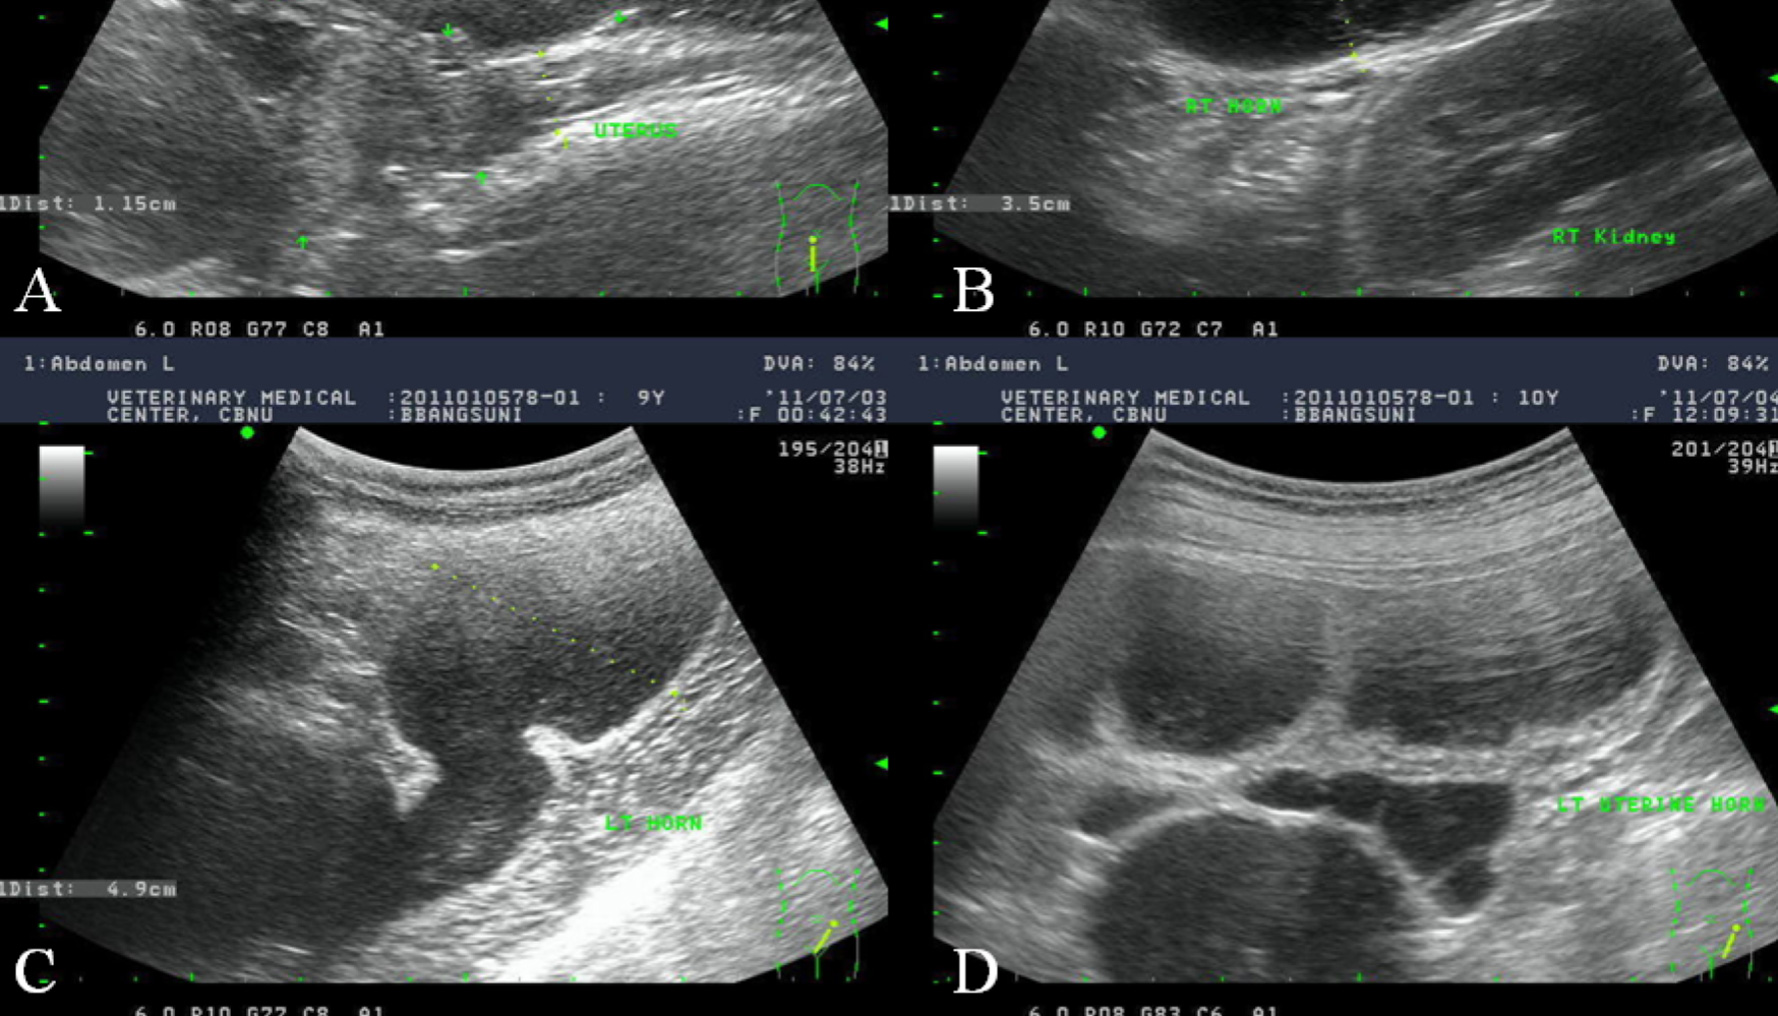

Pyometra

Pyometra is defined as an infection in the uterus. The uterus is also known as the womb and is where the developing foetus is located. It is a serious and life threatening condition that must be treated promptly and aggressively. Pyometra is often the result of hormonal changes in the reproduction in dogs.